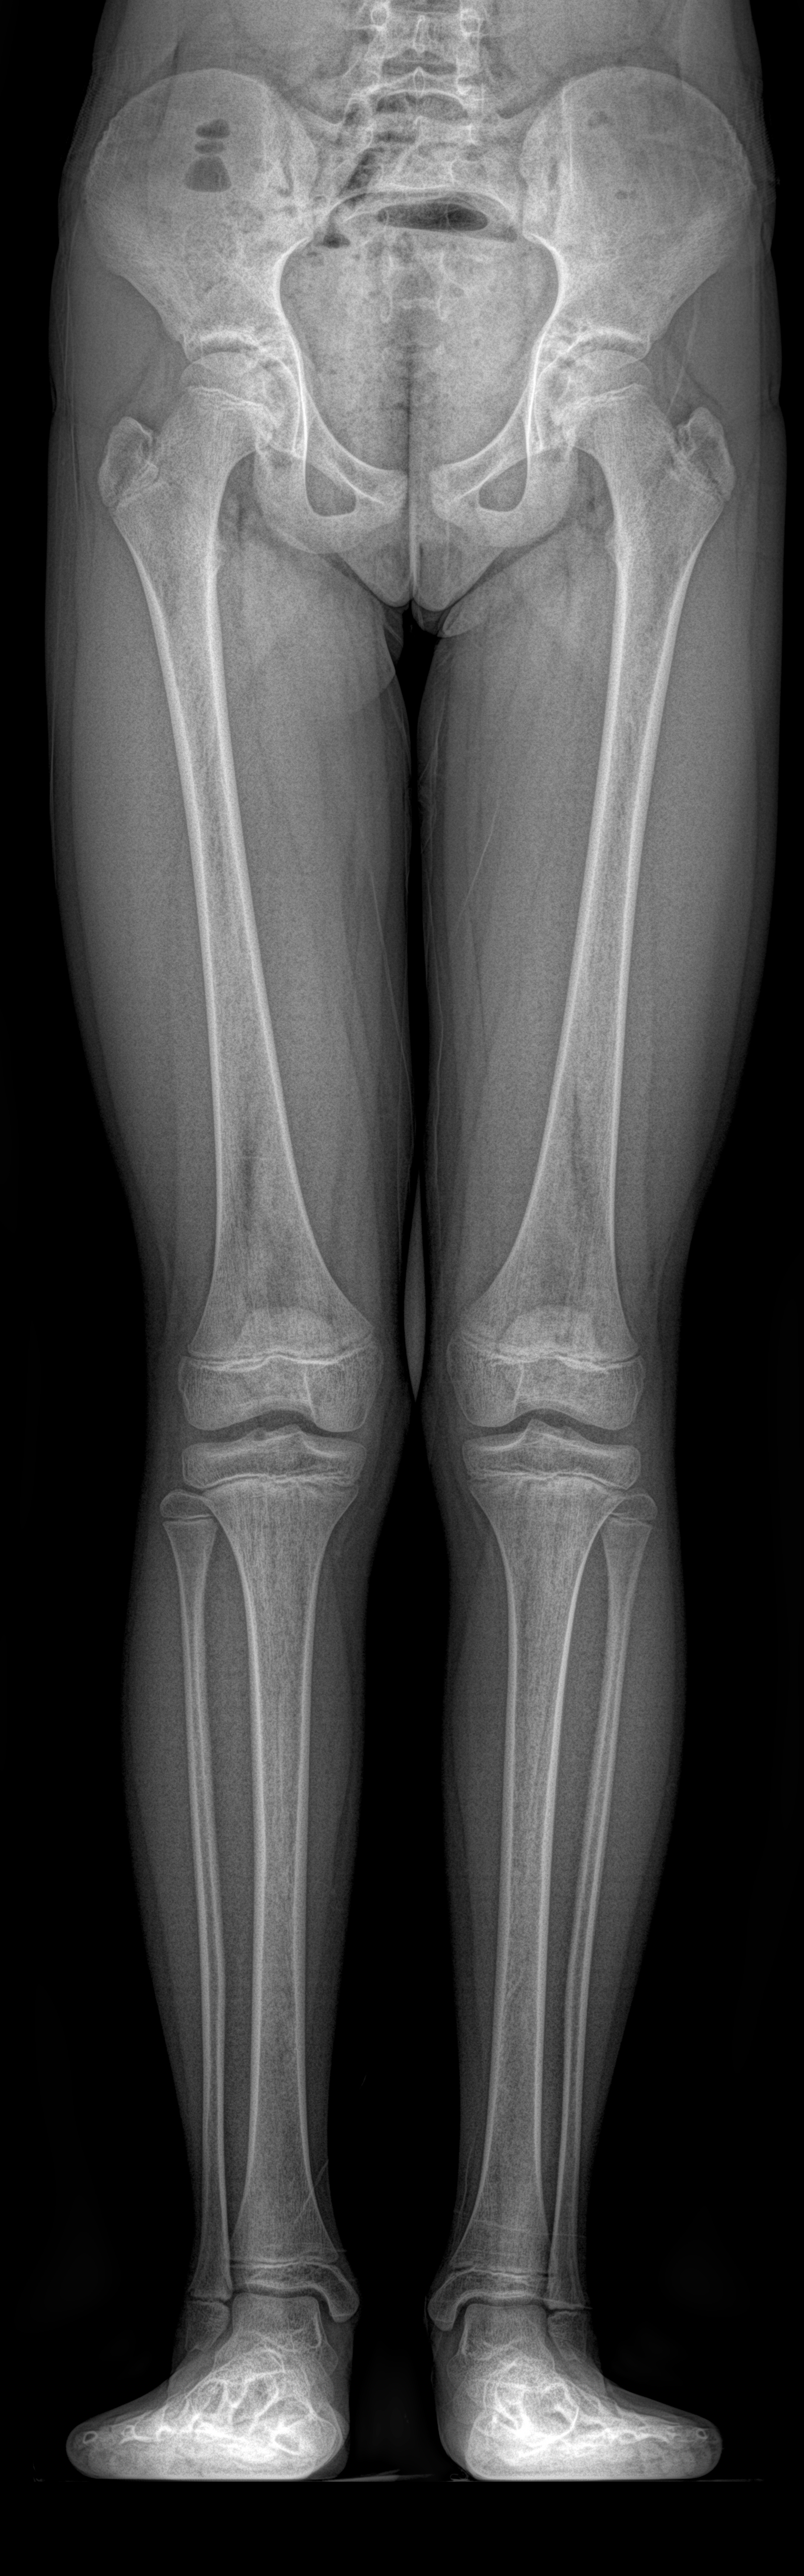

Bacak uzunluğu farklılıklarının milimetrik düzeyde ölçülmesini sağlar. Kliniğimizin EOS çekimleri, cerrahi ve ortopedik yaklaşımlarda doğru kararlar alınmasına katkı sağlar.